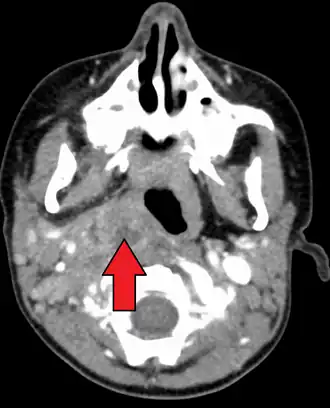

Large retropharyngeal abscess as seen on CT

A computed tomography (CT) scan is the definitive diagnostic imaging test.[4]